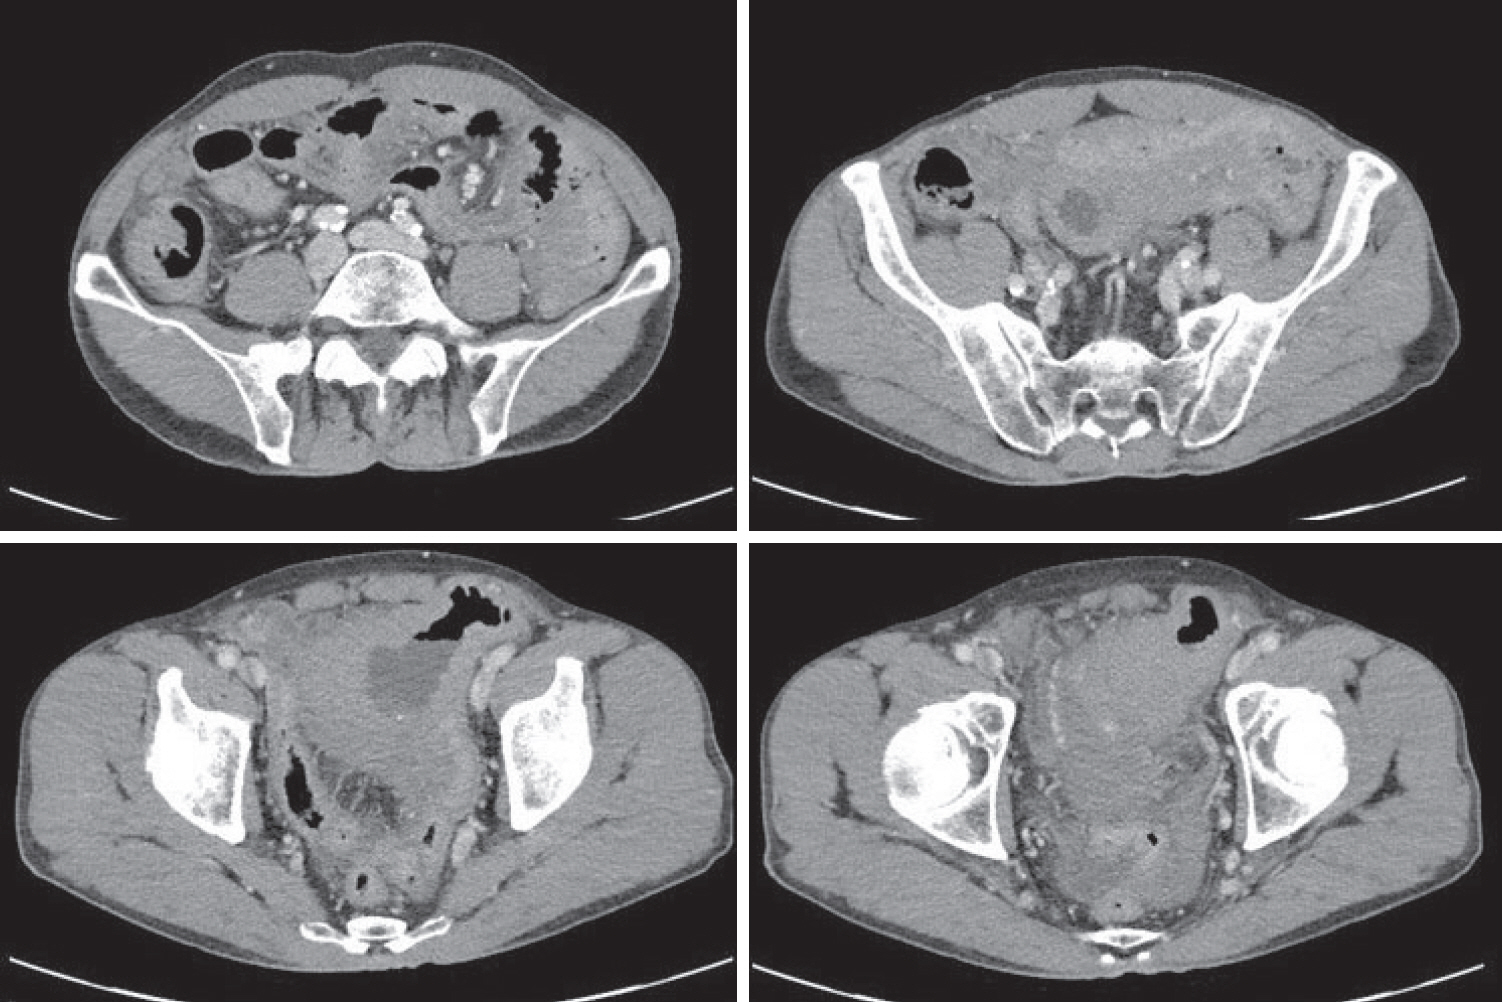

A 70-year-old male underwent sigmoidoscopy after a routine computed tomography (CT) examination, which showed thickening of the sigmoid wall (Fig. 1). Sigmoidoscopy revealed a colonic ulcer, and a biopsy was performed. The lesion was identified as a tubular adenoma; therefore, the patient was referred to the gastroenterology department for repeat biopsy and additional tests. The patient’s medical history included high blood pressure and alcoholic hepatitis. His social history showed that he drank 0.5-1.0 bottle of soju daily and was never a smoker. Information regarding his family history was excluded from the study. The patient had no gastrointestinal symptoms such as abdominal pain or diarrhea, and physical examination findings were unremarkable. Although the biopsy showed a tubular adenoma, the initial colonoscopy indicated that the gross margin of the ulcer was irregularly shaped (Fig. 2), raising suspicion for malignancy. Therefore, despite being asymptomatic, the patient was informed, and another colonoscopy was performed 2 months later. The follow-up examination revealed a scarred sigmoid ulcer located 30 cm from the anal verge, which seemed to have improved compared with the previous findings. Re-biopsy demonstrated features consistent with a simple ulcer (Fig. 3). Accordingly, we concluded that this was a benign colonic ulcer with an inflammatory and ischemic cause rather than cancer, and a follow-up CT scan was sche-duled 1 month later. At the follow-up visit 1 month later, the patient complained of abdominal discomfort after eating for a week, which had not occurred before. He denied having fever, chills, nausea, or vomiting. A subsequent abdominal CT scan showed an approximately 9-cm cavitary lesion abutting the sigmoid colon and urinary bladder dome in the small intestine (Fig. 4). This was accompanied by diffuse nodular omentomesenteric infiltration and peritoneal thickening with small ascites. Based on these findings, the patient was suspected to have a malignant tumor, such as scirrhous carcinoma, inflammatory bowel disease, peritoneal carcinomatosis, or peritonitis, and was referred to a surgeon for surgical treatment. The patient was hospitalized immediately. On admission, the patient complained of abdominal discomfort after eating, and mild generalized abdominal tenderness was noted on physical examination. He was hemodynamically stable. Laboratory testing revealed high white blood cell count of 11.45 × 103/μL (normal range, 4.0-10.0 × 103/μL) with a differential of 67.6% neutrophils (normal range, 38.0-75.0), normal hemoglobin of 16.1 g/dL (normal range, 13.0-17.0), normal platelet count of 151 × 103/μL (normal range, 150-400 × 103/μL), and slightly elevated C-reactive protein level of 7.69 mg/L (normal range, 0.0-5.0). Serum electrolyte and kidney function test results were normal. On the 3rd day of hospitalization, the patient underwent laparoscopic small bowel resection. Immunohistochemical analysis of the resected tissue showed positive staining for CD3, CD4, CD8, CD56, and CAM 5.2 (epithelial marker), and a negative staining for CD10, CD20, CD21, and CD30 (Fig. 5). Histopathological evaluation revealed infiltration by small- to medium-sized T-cell with prominent epitheliotropism, consistent with MEITL. The final diagnosis was MEITL, involving the sigmoid colon, urinary bladder, and peritoneum. Postoperatively, the patient developed persistent ileus with progressive ab-dominal distension and loss of bowel passage, necessitating a second emergency surgery on the 20th day of hospitalization. On the 25th day of hospitalization, the Hemovac drainage became purulent, blood pressure decreased, and the patient went into shock; therefore, a third emergency surgery was performed under the suspicion of bowel perforation. On the 45th day of hospitalization, the patient died of refractory septic shock, presumed to be a complication of intestinal perforation.

Figure 1.

Routine computed tomography (CT) showing thickening of the sigmoid colon wall.